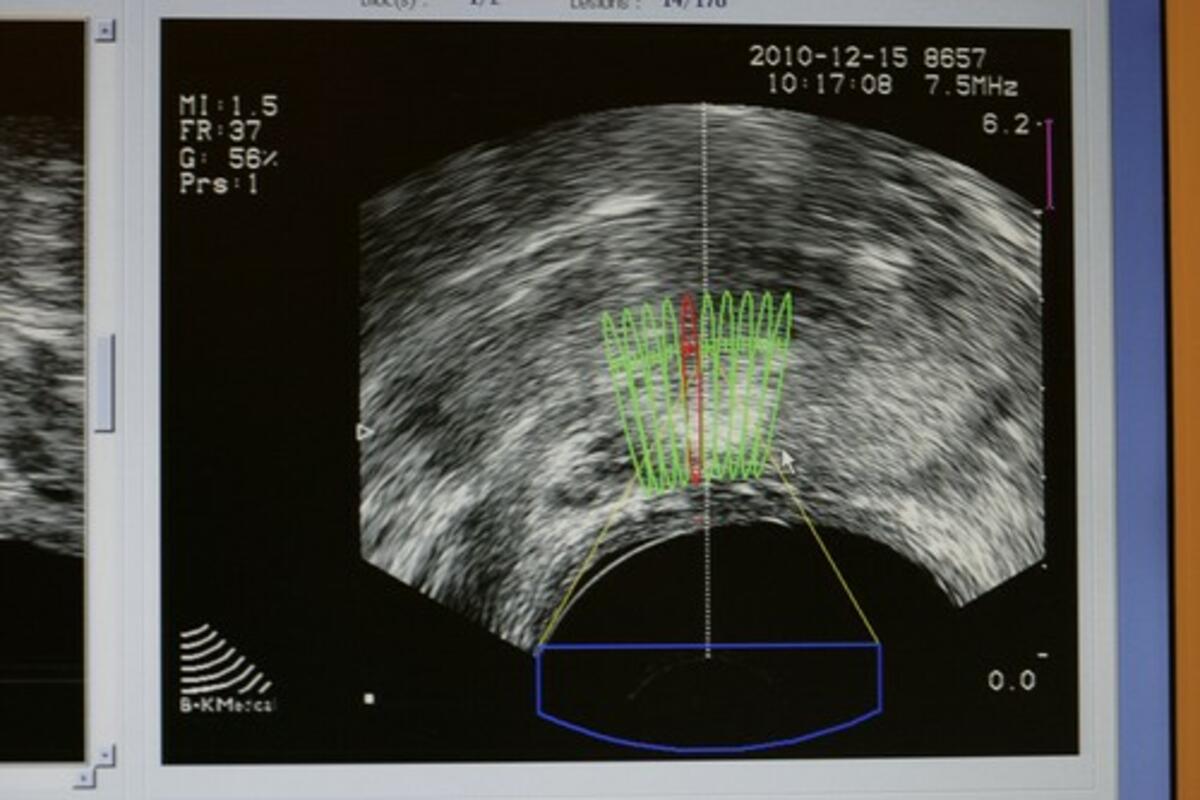

Specijalisti su danas u stanju da smanje broj radioterapija, pošto je ova metoda lečenja postala mnogo preciznija u poslednjih par godina, i da je sada mnogo manje rizika od oštećenja zdravog tkiva, pa jače doze mogu da se primene.

- Kad sam počela pre 15 godina, koristili smo osnovnu radioterapiju, gde smo tretirali velike, kvadratne površine tela. Danas smo mnogo precizniji, i ne zahvatamo zdravo tkivo - rekla je dr Tri.